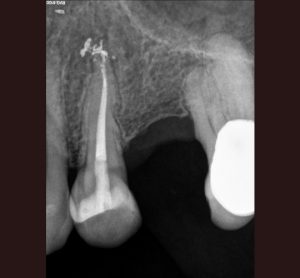

AllAccess Design and ClosureApexificationCBCT DiagnosisCracked TeethCrown Build-upEndodontic MicrosurgeryEndodontic RetreatmentEndodonticsImplantsInternal BleachingMB RootResorption Repair Endodontic Treatment: Case #1- Patient referred due to pain after recent crown cementation. Endodontic Treatment: Case #2 -Patient referred due to pain in her upper first pre molar tooth # 4 Endodontic Treatment: Case #3 – Patient referred due to pain to biting. The amalgam filling was done many years ago. Endodontic Treatment: Case #4 – Patient presented for root canal therapy referred to our office due to complex root anatomy. Endodontic Treatment: Case #5 – Necrotic (dead nerve) tooth with biting pain. Endodontic Treatment: Case #6- Necrotic (dead nerve) tooth with no pain referred for treatment. Endodontic Treatment: Case #7- Very unique tooth with lots of canals (this was a dentists tooth!) Endodontic Treatment: Case #8 – recently prepared for a crown. The patient has cold sensitivity and was referred for treatment. Endodontic Treatment: Case #9- Interesting root anatomy and diagnosis. Endodontic Treatment: Case #10 – 4 canalled lower first molar with 2 distals and 2 mesial canals with a common apex of the mesial root system. Endodontic Treatment: Case #11 Endodontic Treatment: Case #12- Four canalled lower first molar. Finding MB2 The MB Root: Case # 1 The MB Root: Case #2 The MB Root: Case #3 The MB Root: Case #4 The MB Root: Case #5 The MB Root: Case #6 The MB Root: Case #7 The MB Root: Case #8 The MB Root: Case #9 Maxillary MB Root: 1 Mandibular MB Root: 1 Mandibular MB Root: 2 Maxillary MB Root: 2 Mandibular MB Root: 3 Maxillary MB Root: 3 Mandibular MB Root: 4 Endodontic Retreatment: Case #1 – Silver point root canal that was performed 30 years earlier. Endodontic Retreatment: Case #2- Retreatment of initial root canal done 15 years earlier. Endodontic Retreatment: Case #3- Retreatment of a recent root canal performed 2 weeks earlier. Endodontic Retreatment: Case #4 – Retreatment of initial root canal done 12 years earlier Endodontic Retreatment: Case #5 – Retreatment of initial root canal done 30 years earlier. Endodontic Microsurgery: Case #1 Endodontic Microsurgery: Case #2 Endodontic Microsurgery: Case #3 Endodontic Microsurgery: Case #4 Endodontic Microsurgery: Case #5 – Intentional replantation (not so common procedure) Access Closure: Case #1 Access Closure: Case #2 Access Closure: Case #3 Access Closure: Case #4 Access Closure: Case #5 Access Closure: Case #6 Access Closure: Case #7 Access Closure: Case #8 Access Closure: Case #9 Access Closure: Case #10 Access Closure: Case #11 Crown Build-up: Case #1 Crown Build-up: Case #2 Crown Build-up: Case #3 – with bicuspid teeth they are more prone to fracture. Crown Build-up: Case #4 – with bicuspid teeth they are more prone to fracture. Crown Build-up: Case #5 Crown Build-up Case #6 Cracked Teeth: Case #1 Cracked Teeth: Case #2 Cracked Teeth: Case #3 Cracked Teeth: Case #4 Cracked Teeth: Case #5 Cracked Teeth: Case #6 Cracked Teeth: Case #7 Implants: Case #2 Implants: Case #3 Implants: Case #1 Implants: Case #10 Implants: Case #9 Implants: Case #8 Implants: Case #7 Implants: Case #6 Implants: Case #5 Implants: Case #4 CBCT Diagnosis: Case #12 CBCT Diagnosis: Case #11 CBCT Diagnosis: Case #10 CBCT Diagnosis: Case #9 CBCT Diagnosis: Case #8 CBCT Diagnosis: Case #7 CBCT Diagnosis: Case #6 CBCT Diagnosis: Case #5 CBCT Diagnosis: Case #4 CBCT Diagnosis: Case #3 CBCT Diagnosis: Case #2 CBCT Diagnosis: Case #1 High Magnification of Resorption Resorption Repair: Case #5 Resorption Repair: Case #4 Resorption Repair: Case #3 Resorption Repair: Case #2 Resorption Repair: Case #1 Internal Bleaching: Case #3 Internal Bleaching: Case #2 Internal Bleaching: Case #1 Apexification of Lower Premolar